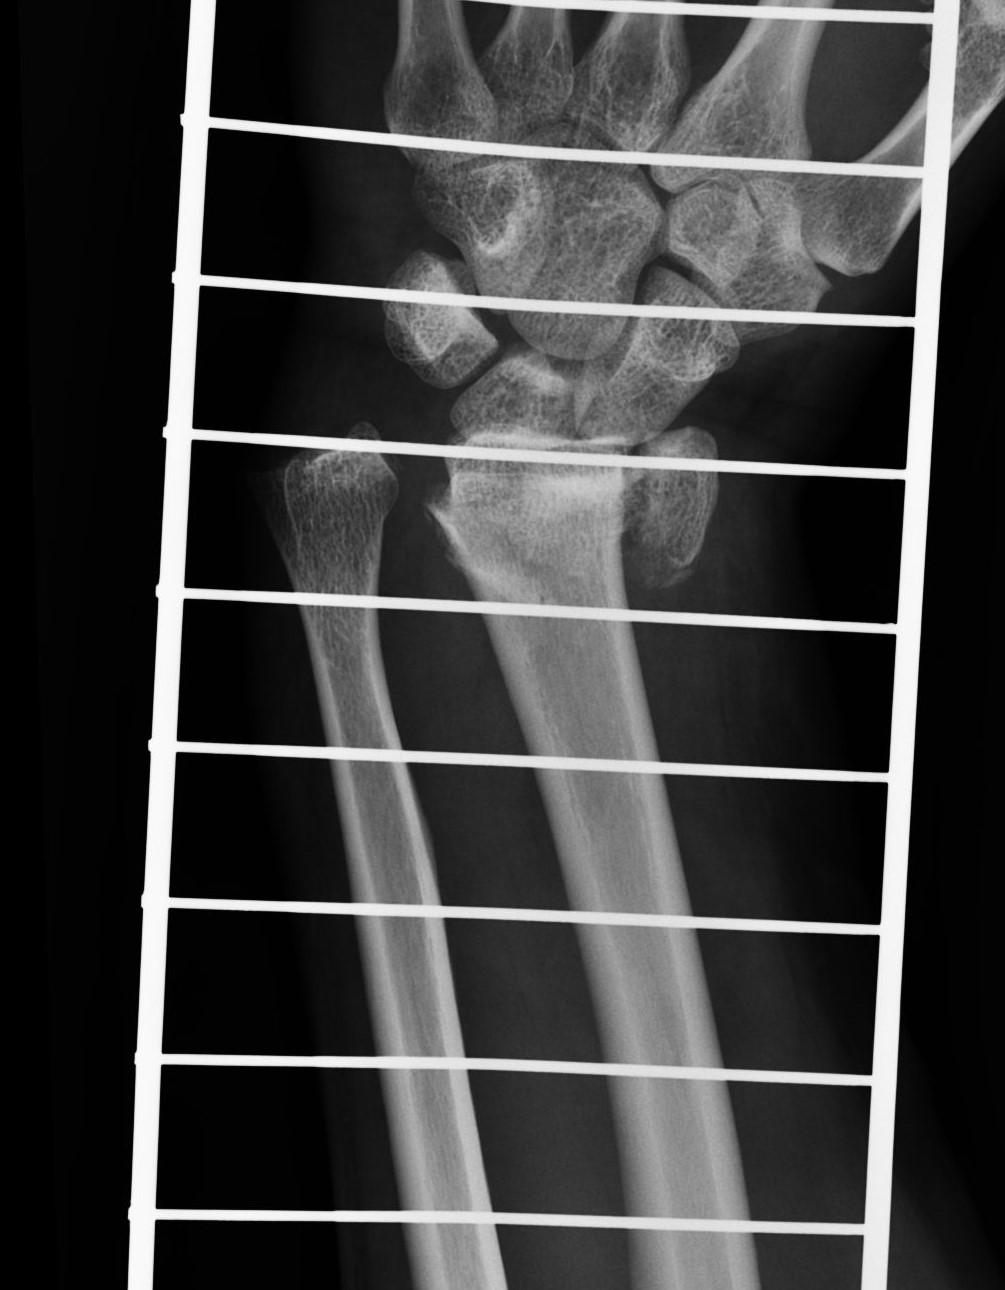

Treatment of neglected, displaced or united distal radial fractures (DRFs) is difficult, because it requires either wedging the almost consolidated fracture and reduction to the correct position, or cutting the united bone and putting it in the correct position (corrective osteotomy). Both treatments are associated with the risk of failure and complications. The paper presents a case of almost fully united DRF in a man, in whom 5 weeks after the injury, and after unsuccessful primary fixation with K-wires, the bone fragments were surgically wedged, aligned and fixed with a palmar plate. The result of treatment after 2 months was satisfactory. Early surgery allowed for a significant shortening of the recovery period and allowed the patient to return to work.